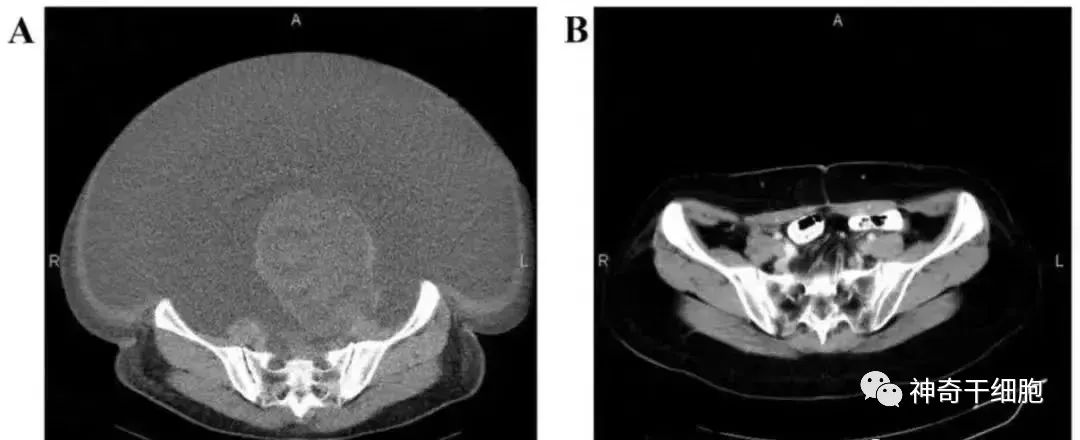

案例2:国内一名60岁的卵巢癌晚期患者,在接受了体外扩增,高度活化的同种异体NK细胞的治疗后,CA125水平从11,270降至580,所有腹水都消失了。此外,CT扫描的肿块体积减小,并且没有出现副作用。